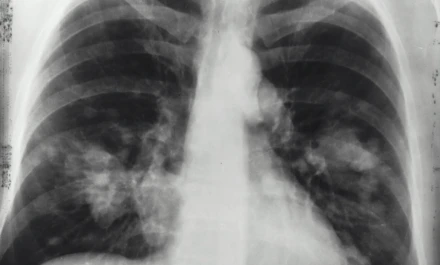

Ο καρκίνος του πνεύμονα είναι η πιο θανατηφόρος μορφή καρκίνου. Παρά την πρόοδο της ιατρικής έρευνας, χιλιάδες ασθενείς χάνουν κάθε χρόνο τη ζωή τους. Ο μη μικροκυτταρικός καρκίνος του πνεύμονα (στην πλειονότητα των περιπτώσεων) συχνά παρουσιάζει αντίσταση στις θεραπείες, με αποτέλεσμα οι όγκοι να επανεμφανίζονται ακόμα και μετά από μία φαινομενικά επιτυχημένη αντιμετώπιση. Αυτό αποτελεί το μεγαλύτερο εμπόδιο για τη μακροχρόνια επιβίωση των ασθενών και οδηγεί τους επιστήμονες να αναζητούν νέες στρατηγικές που θα ξεπεράσουν τα όρια των συμβατικών φαρμάκων.